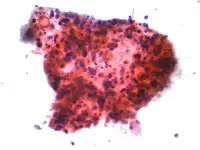

- Fig. 1 - Grappolo di cellule squamose di carcinoma polmonare

- By Nephron (Own work) [CC BY-SA 3.0 (http://creativecommons.org/licenses/by-sa/3.0) or GFDL (http://www.gnu.org/copyleft/fdl.html)], via Wikimedia Commons